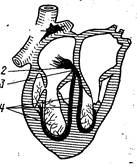

Автоматизм сокращения сердца, закономерная последовательность сокращений предсердий и желудочков на протяжении сердечного цикла обусловлены деятельностью атипичной мышечной ткани, входящей в состав проводящей системы сердца. Эта система состоит из синусно-предсердного узла, расположенного в устье краниальной полой вены, предсердно-желудочкового узла, лежащего в межпредсердной перегородке вблизи места прикрепления створки трехстворчатого клапана, предсердно-желудочкового ствола (пучка Гиса) и его разветвлений, расположенных под эндокардом межжелудочковой перегородки и в соединительнотканных прослойках миокарда — волокна Пуркине (рис. 200). Все эти компоненты проводящей системы образованы атипичными мышечными клетками, которые в функциональном отношении специализированы или на выработке импульса распространяющегося по всему сердцу и вызывающего сокращение его отделов в необходимой последовательности и с определенной частотой (клетки узлов), или на его проведении и передаче сократительным миоцитам.

Автоматизм сокращения сердца, закономерная последовательность сокращений предсердий и желудочков на протяжении сердечного цикла обусловлены деятельностью атипичной мышечной ткани, входящей в состав проводящей системы сердца. Эта система состоит из синусно-предсердного узла, расположенного в устье краниальной полой вены, предсердно-желудочкового узла, лежащего в межпредсердной перегородке вблизи места прикрепления створки трехстворчатого клапана, предсердно-желудочкового ствола (пучка Гиса) и его разветвлений, расположенных под эндокардом межжелудочковой перегородки и в соединительнотканных прослойках миокарда — волокна Пуркине (рис. 200). Все эти компоненты проводящей системы образованы атипичными мышечными клетками, которые в функциональном отношении специализированы или на выработке импульса распространяющегося по всему сердцу и вызывающего сокращение его отделов в необходимой последовательности и с определенной частотой (клетки узлов), или на его проведении и передаче сократительным миоцитам.

Рис. 200. Схема проводящей системы сердца:

1 — синусно-предсердный узел; 2 — предсердно-желудочковый узел; 3 — предсердно-желудочковый ствол (пучок Гиса); 4 — его ножки и разветвления.